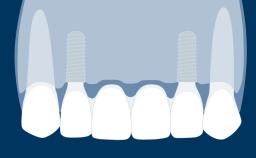

Fixed and removable prosthodontic implant therapy for restoration of the edentulous maxilla is both complex and challenging. Careful assessment and planning is needed in each individual case to explore whether a fixed or a removable solution will be the more suitable to satisfy the patient’s preference for optimal esthetics, phonetics, comfort and function. This Learning Pathway explores the prosthodontically driven treatment planning based on structured assessment, considered diagnosis and practical application in clinical case examples.